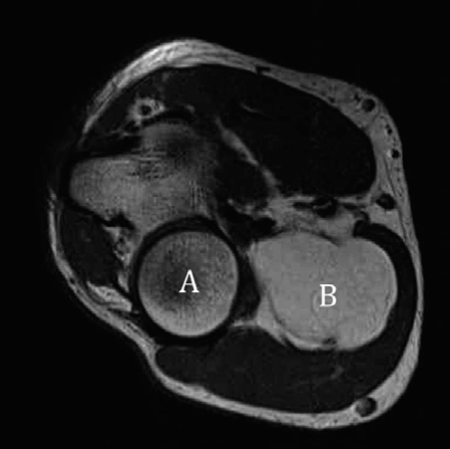

Orthopaedic oncology Structured oral examination question 9: Lipoma EXAMINER : This is an MRI of a patient wh…